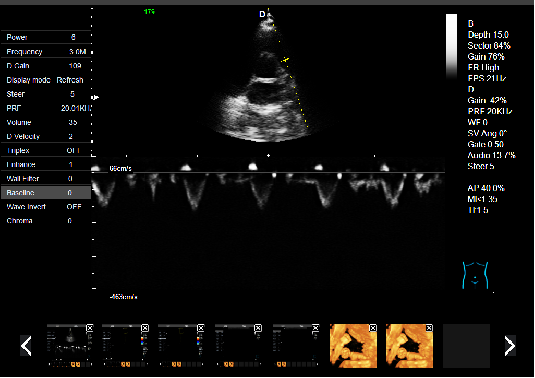

心臟超聲檢查:

心臟超聲是唯一能動(dòng)態(tài)顯示心腔內(nèi)結(jié)構(gòu)、心臟的搏動(dòng)和血液流動(dòng)的儀器,對(duì)人體沒(méi)有任何損傷。心臟的各個(gè)結(jié)構(gòu)清晰地顯示在屏幕上。通過(guò)彩超的測(cè)量,醫(yī)生可了解瓣膜病變的程度以決定保守治療還是手術(shù)治療。心肌的增厚、心腔的擴(kuò)大都要依賴彩超來(lái)判斷;對(duì)冠心病,彩超能直觀顯示心肌的運(yùn)動(dòng)狀況及心功能,向臨床醫(yī)生提示心肌缺血的部位。